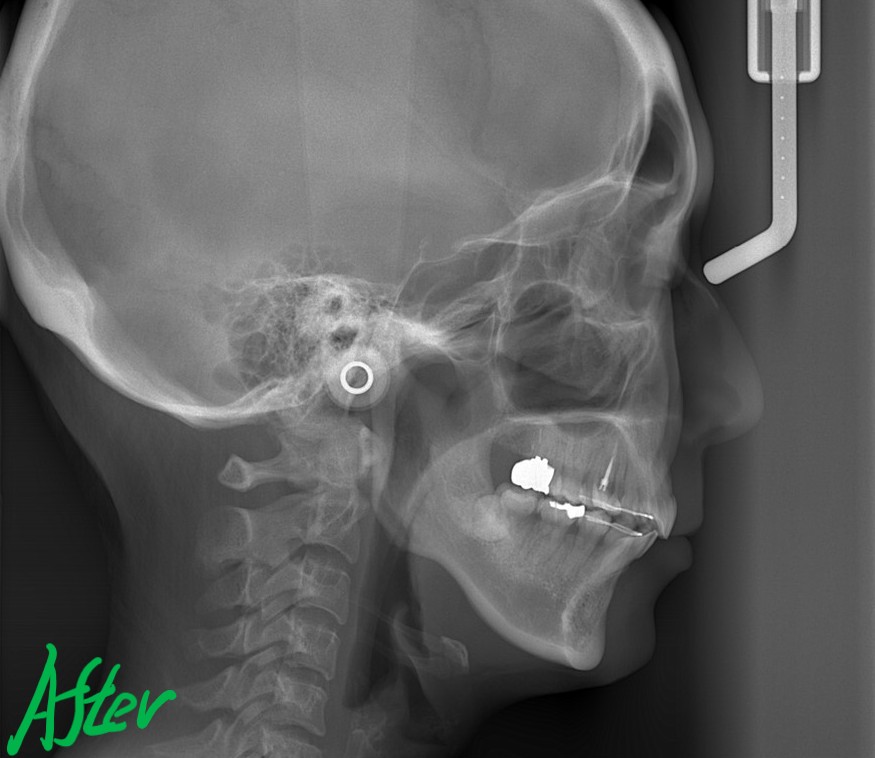

レントゲン写真でも矯正治療前後を比較してみましょう